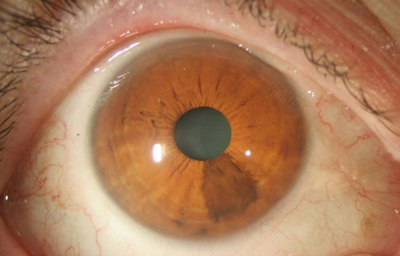

Nevus melanociticos en el Iris

Archivo Fotográfico Dr. Francisco Barraquer

Nevus melanociticos en el Iris

Archivo Fotográfico Dr. Francisco Barraquer

Nevus con escaso pigmento

Archivo Fotográfico Dr. Francisco Barraquer

Nevus melanocítico en el Iris -“Nevus”

Estas lesiones que pueden ser pigmentadas o no, muestran más penetración en el estroma con distorsión, pudiendo producir ectrópion y corectópia. La célula névica es una variante del melanocito, son más grandes no tienen dendrítas y tienen un citoplasma granular mas abundante. En angiografía se aprecia que no tienen vascularización

Se considera que los adquiridos son neoplasmas benignos, mientras que los congénitos (perinatales) son considerados con un mayor riesgo de malignización.